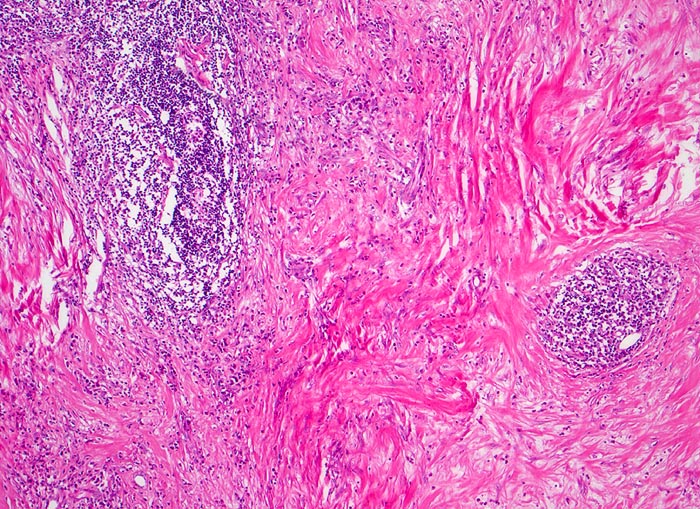

Hodgkin-Lymphom, noduläre Sklerose

Zerstörung der regulären Zonierung und Gliederung des Lymphknotens durch breite Kollagenfaserstränge, welche Knoten von lymphatischem Gewebe abgrenzen.

Mediastinaler Tumorbulk.